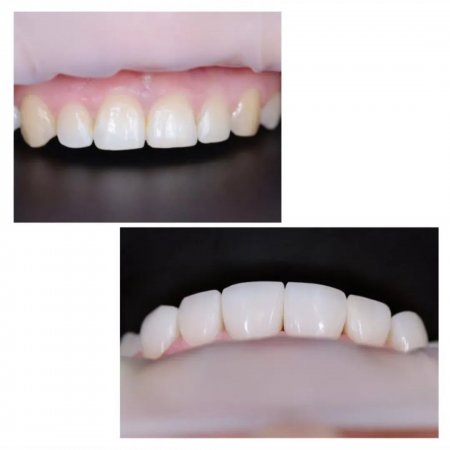

Сучасна стоматологія дозволяє відновити втрачені зуби настільки природно, що відрізнити імплант від власного зуба практично неможливо. Саме тому дедалі більше кременчужан обирають цей метод лікування.

Як підібрати імпланти правильно? Стоматологи радять звертати увагу на якість матеріалів, гарантії виробника та досвід лікаря. Від цього залежить не лише комфорт, а й довговічність результату.

Клініка «Мрія» у Кременчуці працює за перевіреними методиками, які дозволяють відновити усмішку всього за 7 діб — навіть у випадках повної відсутності зубів. Лікарі обирають рішення індивідуально, щоб кожен пацієнт отримав стабільний і передбачуваний результат.